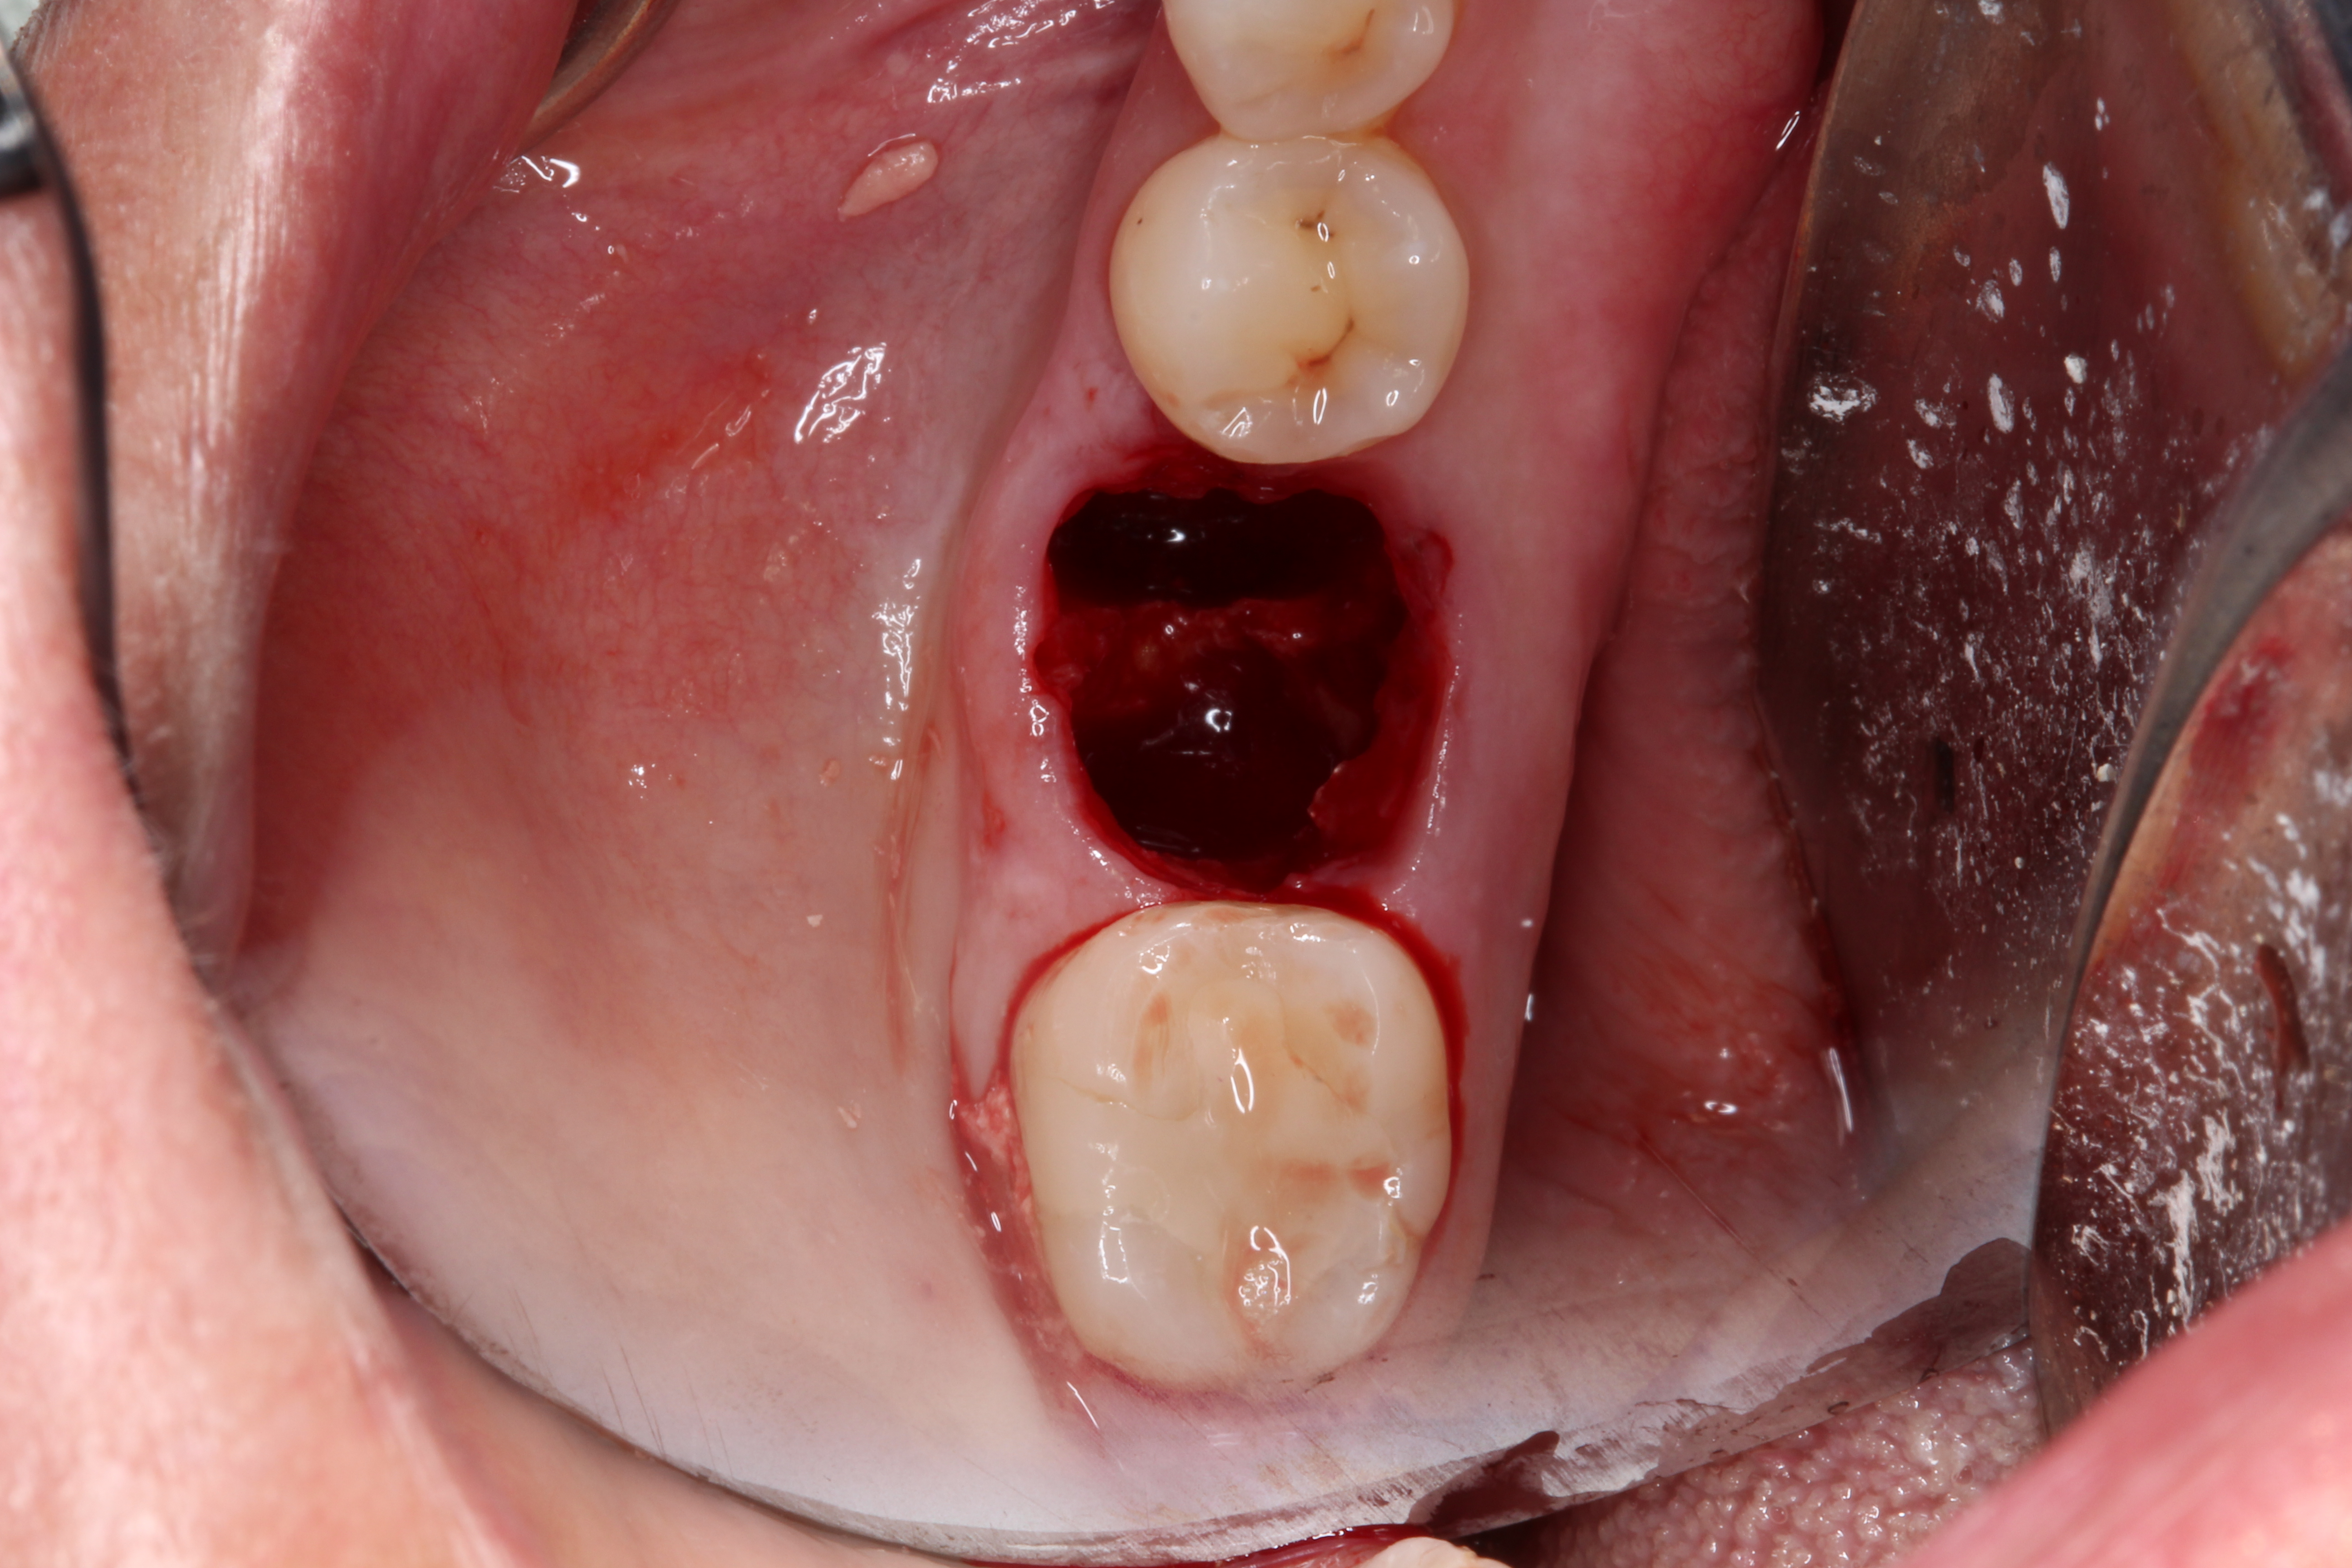

3. Make sure the socket is bleeding (Figure 6). If necessary, decorticate the remaining socket walls, using a round bur or surgical-type bur, to create a bleeding wound that will facilitate early vascularization and the beginning of the primary healing cascade.

Fig 6.The socket must be bleeding before delivering the graft material. This facilitates the healing cascade and greatly increases the success of the socket preservation.

Figure 6